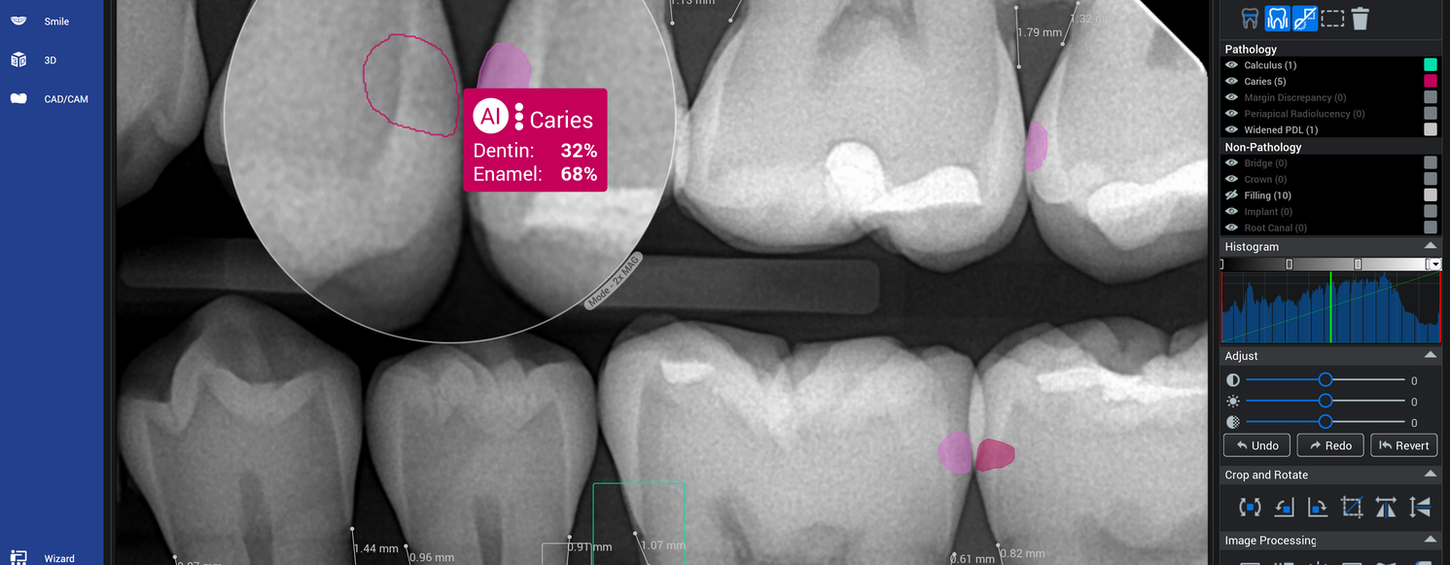

Možnost volitelné nadstandardní AI analýzy obrazu, barevné zvýraznění možných patologických změn (možno i pro importované snímky při odpovídající kvalitě).

ENDO

CBCT - Al pomáhá stomatologovi tím, že poskytuje detailní 3D pohled na kořenové kanálky, umožňuje jejich automatické zvýraznění a měření, zvyšuje bezpečnost ošetření a snižuje riziko komplikací. V kombinaci s mikroskopem to vede k přesnější diagnostice, efektivnějšímu ošetření a lepší prognóze zubů.